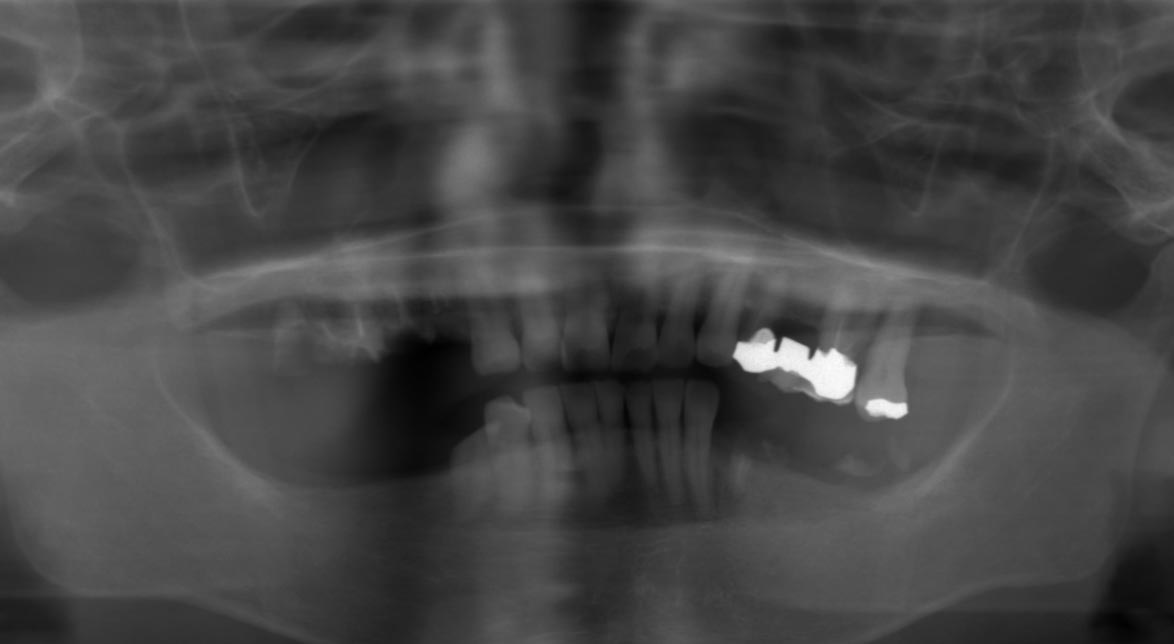

写真(レントゲン写真)

右上、左下の歯はむし歯が進行して、根だけの状態になっていました。 左上のブリッジ(レントゲン写真で真っ白に写っているもの)の下はむし歯が進行し、一番奥の歯は歯周病でグラグラな状態でした。 検査の結果、上下とも奥歯を残すことは難しい状態となっていました。